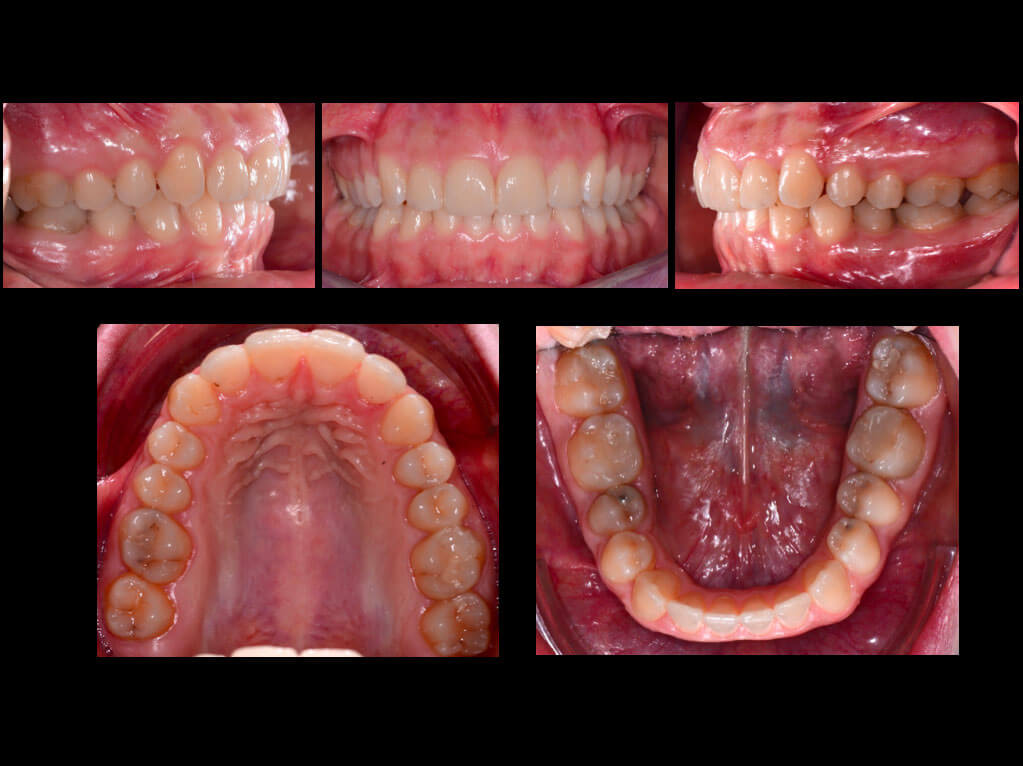

Una giovane paziente giunge alla nostra attenzione per un diastema tra gli incisivi centrali superiori. Il volto era simmetrico e le labbra competenti, mentre il profilo evidenziava una certa retrusione mandibolare. A livello occlusale la paziente mostrava una debole prima classe molare e canina con presenza di numerosi diastemi soprattutto all’arcata superiore; non riferiva peraltro problemi articolari, ma aveva una gengivite marginale per una igiene orale non ottimale.

L’analisi clinica chiarisce che il problema è rappresentato dalla dimensione degli incisivi superiori. Questo significa che la chiusura dei diastemi per arretramento del gruppo frontale e stripping inferiore non sarebbe stata un’ottima soluzione perché dal punto di vista estetico avrebbe reso ancora più evidente la dimensione ridotta degli incisivi; inoltre questa soluzione avrebbe significato anche un peggioramento dell’inclinazione dei denti rispetto alle basi ossee e ai tessuti molli. In questo caso l’unica possibilità è combinare il trattamento ortodontico con l’aggiunta di sostanza dentale all’arcata superiore a livello degli incisivi al fine di aumentarne l’altezza. Lo scopo della terapia ortodontica sarebbe stato quello di distribuire gli spazi in maniera ideale facilitando l’attività del protesista ed evitando un’eccessiva lingualizzazione.

Prima

È stato eseguito un set-up che ha permesso di pianificare i movimenti sulla base delle necessità protesiche e che ha anche mostrato la necessità di eseguire una certa quantità di stripping all’arcata inferiore. Sono stati pianificati 14 allineatori superiori e 14 inferiori ed è stato necessario mettere i grip point sui primi premolari e sui primi molari di entrambe le arcate per migliorare l’ancoraggio dell’allineatore.